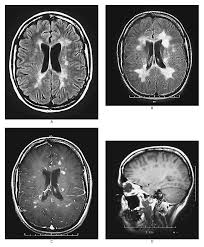

La esclerosis múltiple (EM) se conoce desde hace más de 100 años; una de las primeras descripciones fue el caso de Santa Ledwima de Schiedman, cuya sintomatología consistía en dificultad para movilizar una de las extremidades inferiores, problemas para pasar los alimentos, alteraciones en la visión y trastornos en la sensibilidad. La enfermedad fue descrita con más detalle por Jean Cruveilhier (1835) y Robert Carswell (1838). Más tarde, en 1860, Jean-Martin Charcott describió que los síntomas eran atribuibles a lesiones de la sustancia blanca que forma parte de las fibras del sistema nervioso central y que está recubierta por un compuesto llamado mielina.

Esta enfermedad es un trastorno inflamatorio donde las respuestas autoinmunes son dirigidas a la destrucción de las proteínas de la capa de mielina del sistema nervioso central. En otras palabras, el propio organismo daña específicamente a las prolongaciones de las neuronas (axones) que son las que llevan la información a las partes distantes de nuestro cuerpo, y como éstas se encuentran revestidas de mielina al perderse ésta se hace un "corto-circuito" y la información trasmitida es alterada dando la sintomatología más diversa e incongruente que se puede imaginar.